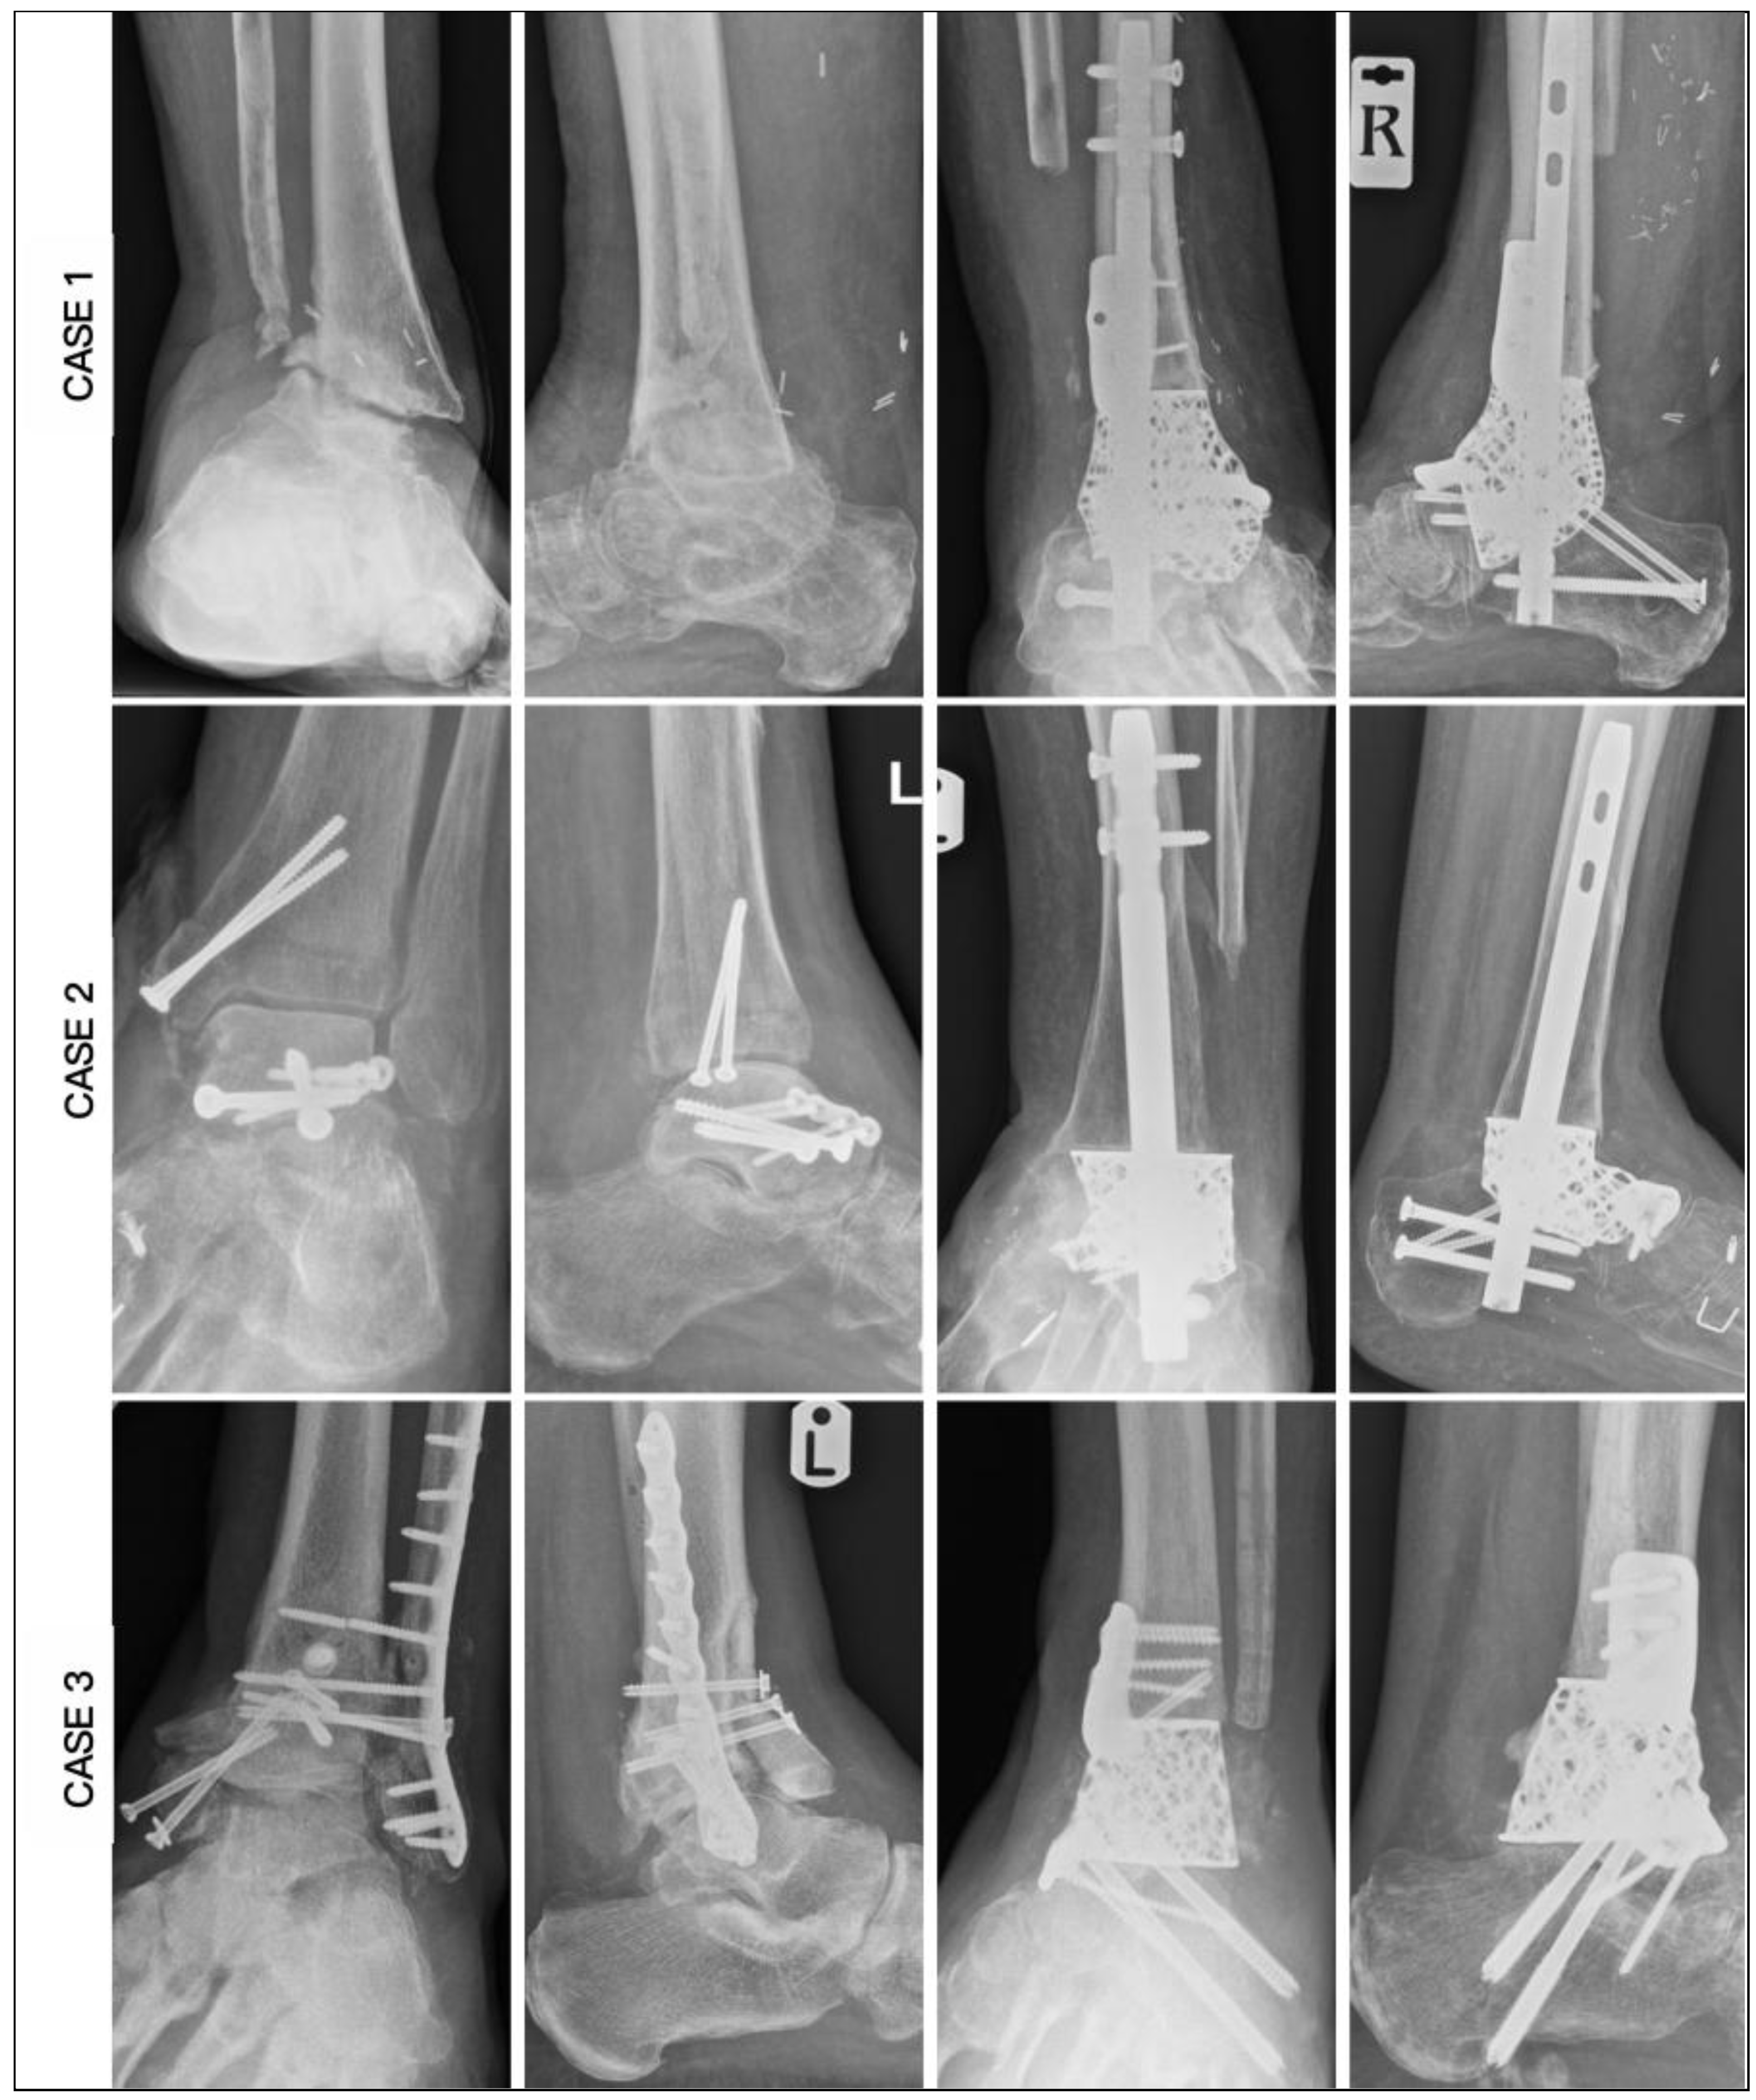

| CASE | 1 | 2 | 3 | 4 | 5 | 6 |

|---|---|---|---|---|---|---|

| Age | 62 | 59 | 60 | 60 | 78 | 67 |

| Diagnosis | OM | OM | OM | AVN | AVN | AVN |

| Smoking | No | Yes | Yes | No | Yes | No |

| BMI | 26.5 | 27.4 | 27.4 | 28.2 | 32.1 | 35.4 |

| Medical | Nil | IHD, CKD, PAD | CKD | CKD, PAD | DM | IHD, DM, CKD, CN |

| HbA1c | 36 | 39 | 39 | 41 | 49 | 70 |

| CRP | 8 | 7 | 16 | 9 | 10 | 6 |

| Hb (g/L) | 113 | 105 | 132 | 146 | 113 | 114 |

| Past surgery | 5 | 3 | 3 | 0 | 1 | 0 |

| Modification | Tibial & Navicular flange, Nail | Navicular flange, Nail | Tibial & Navicular flange | Navicular flange, Nail | Nail | Articulating Navicular extension, Tibial flange, Nail |

| Duration of surgery (Min) | 255 | 220 | 162 | 210 | 190 | 205 |

| Wound Healing (Days) - weeks | 42 | 40 | 20 | 29 | 32 | 45 |

| Union (Weeks) | 25 | 19 | 16 | 14 | 27 | 20 |

| Ambulation (Weeks) | 28 | 21 | 18 | 16 | 29 | 22 |